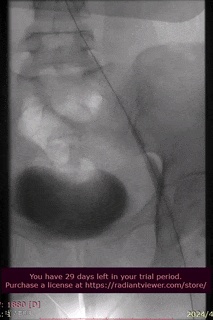

手术过程